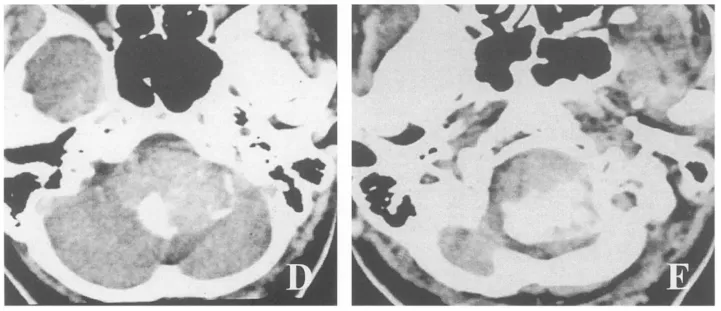

术前CT

CT的骨质结构显示较MRI清晰,部分肿瘤对骨性结构具有侵袭性和破坏性。CT的三维显像技术的发展使得颅颈交界区的骨质结构及血管三维结构重建成为现实,能够立体直观的提供患者枕骨大孔、寰椎、枢椎等颅底骨质结构及肿瘤与重要血管之间的关系,呈现肿瘤周围重要血管、神经、骨质结构的立体空间关系,可见肿瘤明显强化呈典型的“瘤染色”特征,有助于指导手术入路的选择、骨质的移除及术中暴露肿瘤并保护重要血管神经。